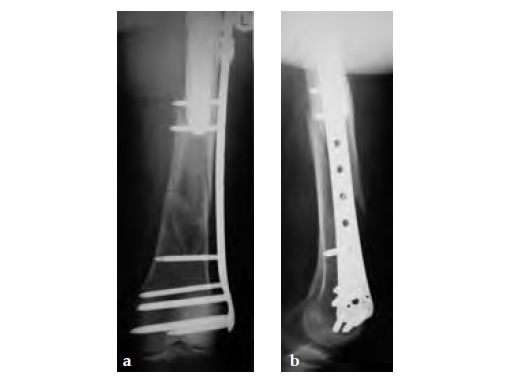

Case provided by Michael Wagner, Wien, Austria.

Case 2: A 76-year-old female with a Vancouver type C fracture.